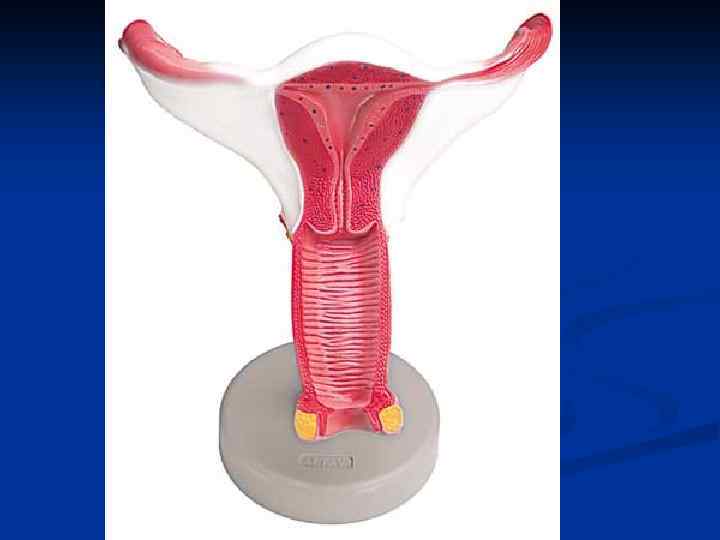

Женские половые органы, organa genitalia feminina

Женские половые органы, organa genitalia feminina

Контрацепция ВМС – Внутри. Маточная Спираль (Внутри. Маточные Средства)

Контрацепция ВМС – Внутри. Маточная Спираль (Внутри. Маточные Средства)

Рис 1 (норма) Гистерограмма: 1 — перешеек матки, 2 — канал шейки матки, 3 — катетер, через который введено рентгеноконтрастное вещество; видно значительное расширение перешейка и канала шейки матки. Рис 2 И стмико-цервика льная недоста точность (insufficientia isthmicocervicalis; Истмико+ анат. cervix uteri шейка матки) -нарушение функции шейки и перешейка матки, проявляющееся зиянием шейки матки, приводящим к самопроизвольному прерыванию беременности; возникает в результате повреждения миометрия или при нарушении гормональной регуляции.

Рис 1 (норма) Гистерограмма: 1 — перешеек матки, 2 — канал шейки матки, 3 — катетер, через который введено рентгеноконтрастное вещество; видно значительное расширение перешейка и канала шейки матки. Рис 2 И стмико-цервика льная недоста точность (insufficientia isthmicocervicalis; Истмико+ анат. cervix uteri шейка матки) -нарушение функции шейки и перешейка матки, проявляющееся зиянием шейки матки, приводящим к самопроизвольному прерыванию беременности; возникает в результате повреждения миометрия или при нарушении гормональной регуляции.